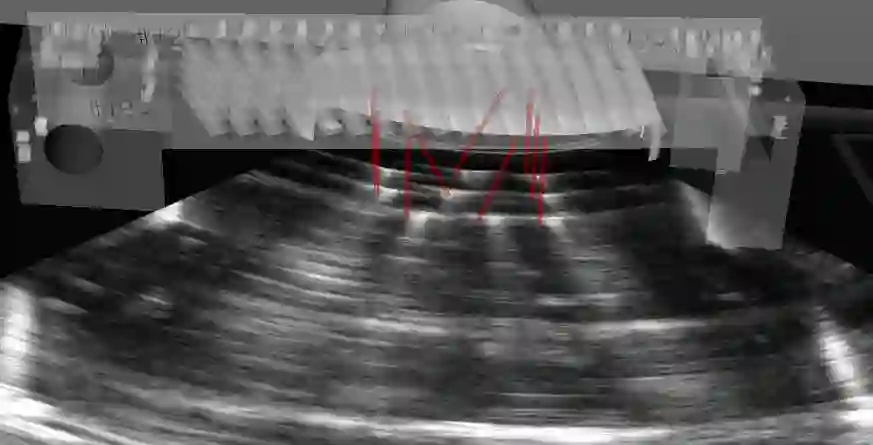

Purpose. Ability to locate and track ultrasound images in the 3D operating space is of great benefit for multiple clinical applications. This is often accomplished by tracking the probe using a precise but expensive optical or electromagnetic tracking system. Our goal is to develop a simple and low cost augmented reality echography framework using a standard RGB-D Camera. Methods. A prototype system consisting of an Occipital Structure Core RGB-D camera, a specifically-designed 3D marker, and a fast point cloud registration algorithm FaVoR was developed and evaluated on an Ultrasonix ultrasound system. The probe was calibrated on a 3D-printed N-wire phantom using the software PLUS toolkit. The proposed calibration method is simplified, requiring no additional markers or sensors attached to the phantom. Also, a visualization software based on OpenGL was developed for the augmented reality application. Results. The calibrated probe was used to augment a real-world video in a simulated needle insertion scenario. The ultrasound images were rendered on the video, and visually-coherent results were observed. We evaluated the end-to-end accuracy of our AR US framework on localizing a cube of 5 cm size. From our two experiments, the target pose localization error ranges from 5.6 to 5.9 mm and from -3.9 to 4.2 degrees. Conclusion. We believe that with the potential democratization of RGB-D cameras integrated in mobile devices and AR glasses in the future, our prototype solution may facilitate the use of 3D freehand ultrasound in clinical routine. Future work should include a more rigorous and thorough evaluation, by comparing the calibration accuracy with those obtained by commercial tracking solutions in both simulated and real medical scenarios.